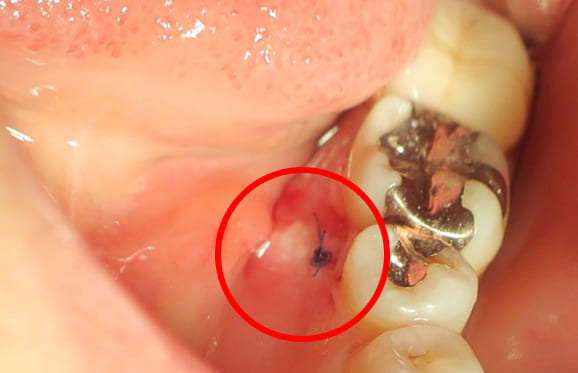

● 下の顎の親知らず抜歯 1回法

藤沢デンタルオフィスの親知らず抜歯